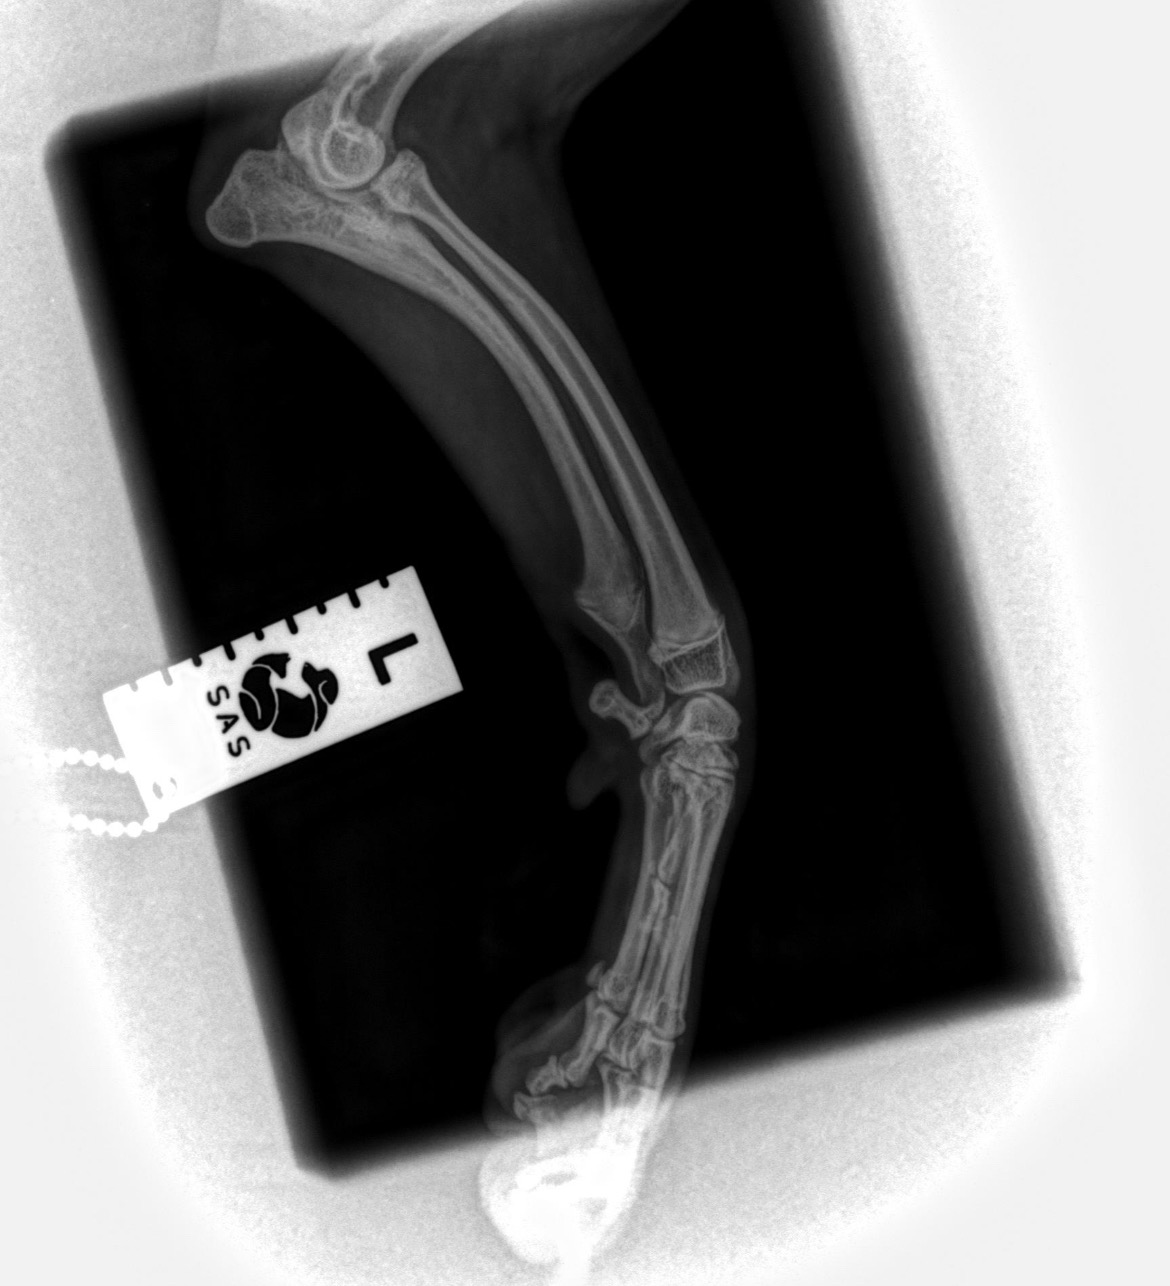

We first had concerns about Goofy's wellbeing after he'd been limping for a few weeks after getting his first grooming. Unfortunately, because we struggle financially, we couldn't get him seen by a vet as quickly as we'd like to, but we got him checked, including x-rays, as soon as we could. Sadly, the vet diagnosed Goofy with a Valgus Malformation (genetic malformation in his front leg), which, if left untreated before Goofy is a year old, will mean that he won't be able to walk properly, leading to constant pain and further related difficulties - and whilst long-term medical treatment may help him, this option is not in his best interest and will be more expensive in the long term.

I am a full-time student but have luckily been able to find a part-time job to fit around my studies, so that I can save money toward the consultation and surgery costs, which will be around £4000. However, as Goofy has just turned 8 months old and will need the surgery by 15th December, I don't have enough time to save the amount needed. So, I am appealing to you and asking for your donation, however big or small - every penny will help get my precious Goofy the surgery he desperately needs.